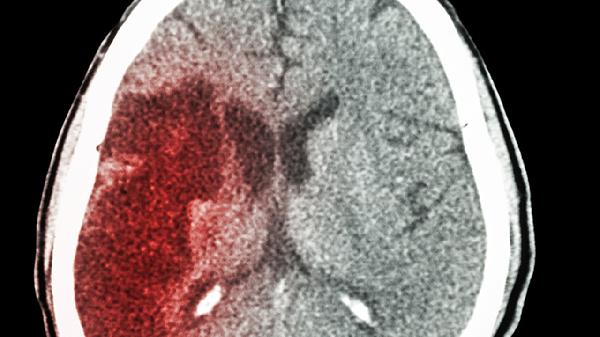

手指发麻可能是身体发出的"求.救信号"!最近一位50多岁的大叔,就因为持续两个月的手指发麻没当回事,结果检查发现是脑梗前兆。这种看似普通的症状,背后可能藏着健康隐患。

当手麻同时出现头晕、言语不清、面部不对称等情况,必须立即就医,这可能是脑卒中的前兆表现。